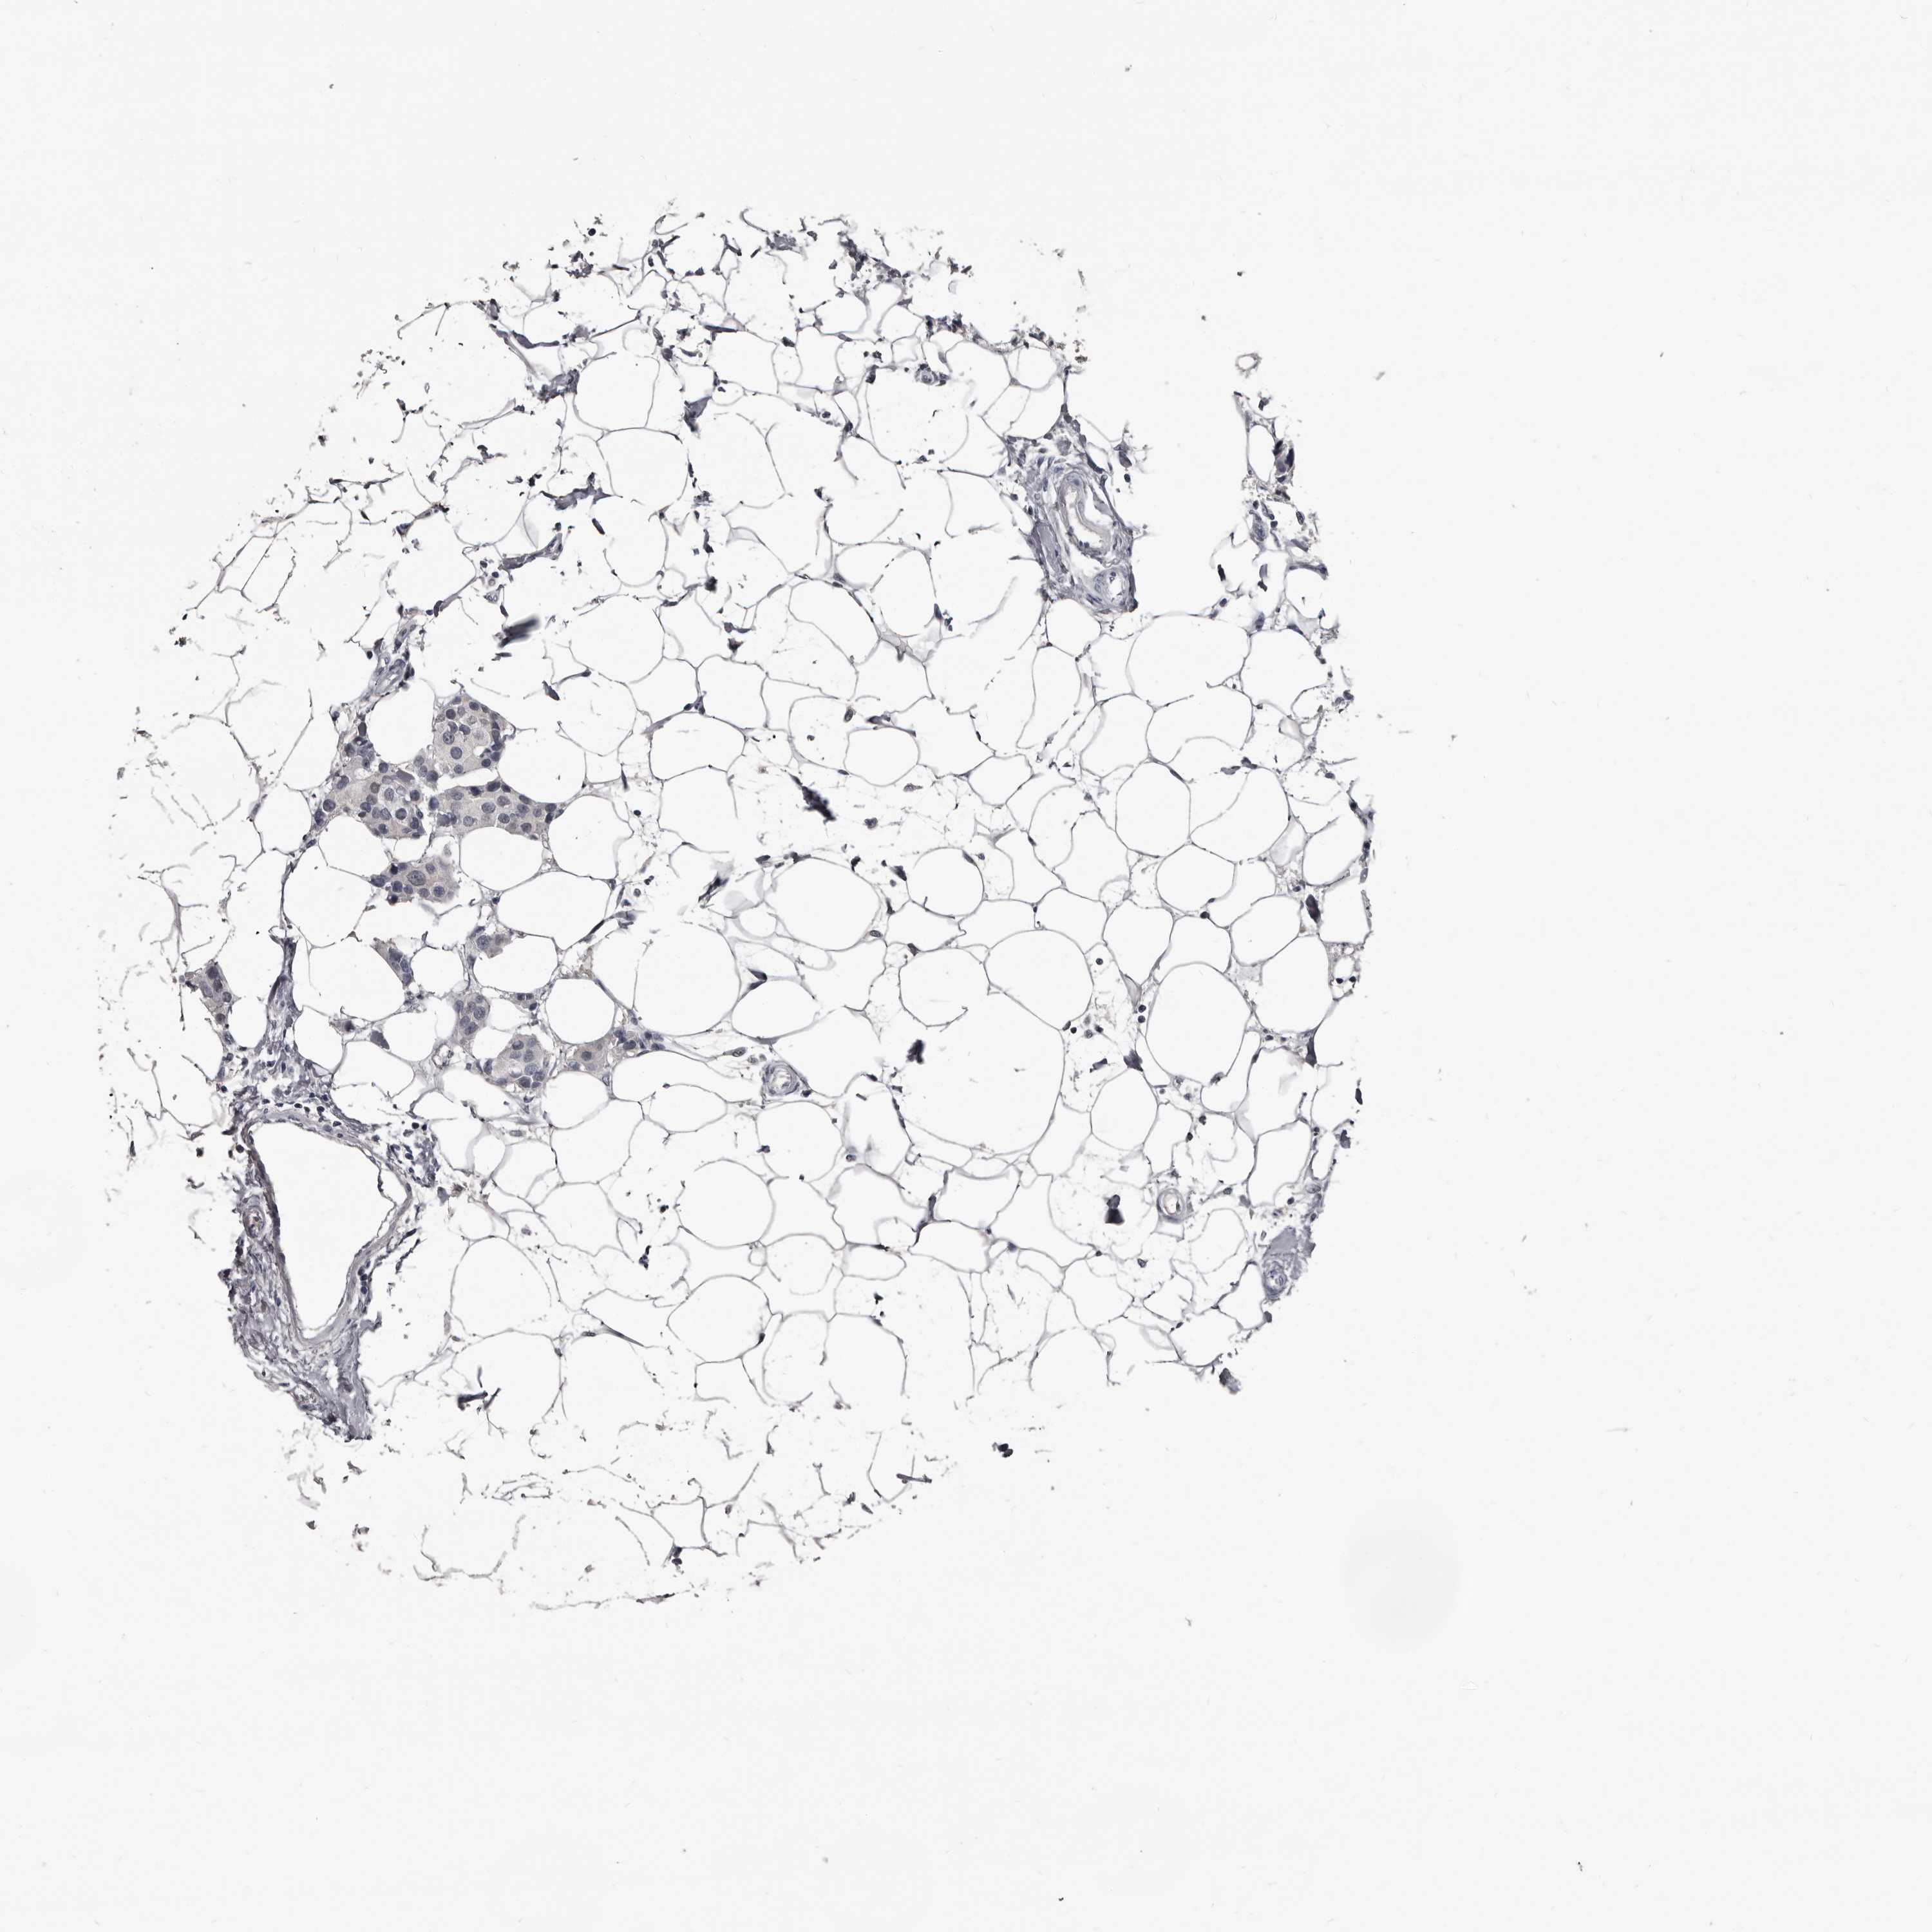

CANCER BREAST CANCER Show tissue menu

BRCA TCGA BRCA VALIDATION PROTEIN EXPRESSION

ANTIBODIES

AND

VALIDATION